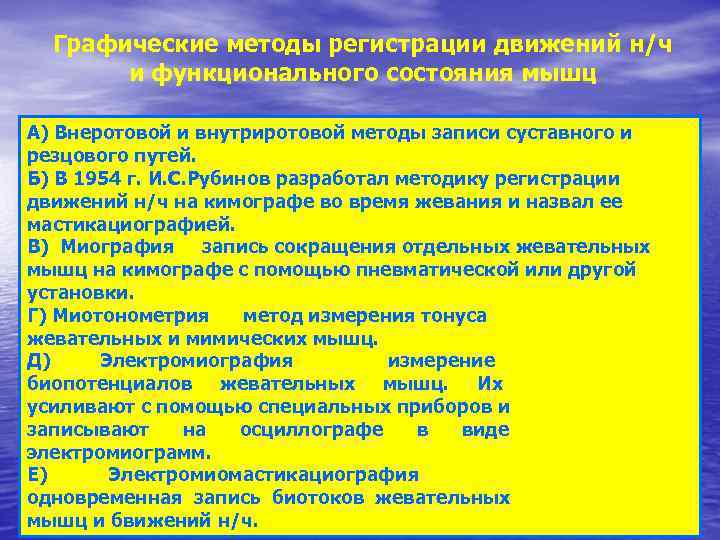

Графические методы регистрации движений н/ч и функционального состояния мышц A) Внеротовой и внутриротовой методы записи суставного и резцового путей. Б) В 1954 г. И. С. Рубинов разработал методику регистрации движений н/ч на кимографе во время жевания и назвал ее мастикациографией. B) Миография запись сокращения отдельных жевательных мышц на кимографе с помощью пневматической или другой установки. Г) Миотонометрия метод измерения тонуса жевательных и мимических мышц. Д) Электромиография измерение биопотенциалов жевательных мышц. Их усиливают с помощью специальных приборов и записывают на осциллографе в виде электромиограмм. Е) Электромиомастикациография одновременная запись биотоков жевательных мышц и бвижений н/ч.